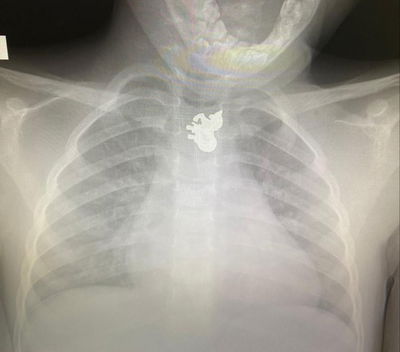

במשך יותר מחודש וחצי התינוק הקטן סבל מרצף הקאות בלתי פוסק, רופאי המשפחה אמרו כי "זה רק וירוס קטן", האמא התעקשה לעשות לו צילום - והפתיעה את הרופאים (בריאות)